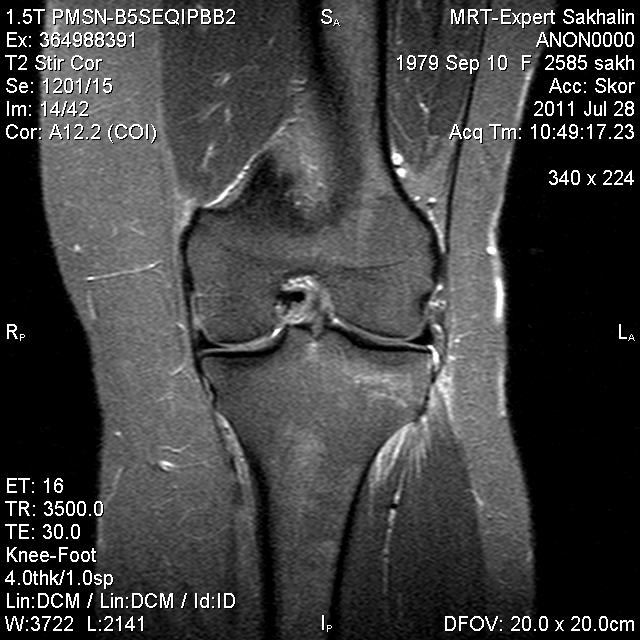

Коленный сустав

Подглядела случай у коллеги.

Что это может быть?

Не вижу криминала. А на что жалуется девушка?

P.S. В костях - это, скорее всего, резидуальный красный костный мозг.

Жалоба у всех одна на всех-болит.

участки гемопоэтического костного мозга